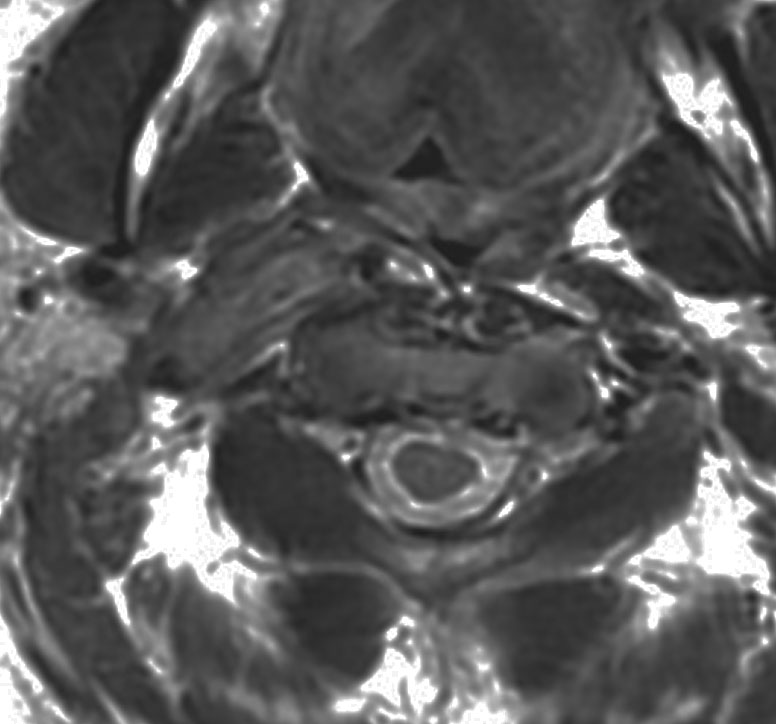

症例:頸静脈孔から頭蓋内へのもの

頸静脈孔を中心に頭蓋底骨の破壊 erosionがみられます。小脳延髄角部に進展して延髄を圧迫しています。聴神経を圧迫して聴力低下で発見された,迷走神経鞘腫です。頸静脈孔内発生のものは脳槽内の迷走神経根から腫瘍を剥離することができます。

手術直後のMRIです。頸静脈孔より深い位置にある腫瘍まで摘出しようとすると,舌咽,迷走,副神経を損傷しますから,最深部の部分だけ残して摘出しました。

手術後14年が経過しますが,無治療で残存腫瘍は縮小しました。術後神経鞘腫の自然経過ではよく観られることです。

ですから,無理して全摘出しない。